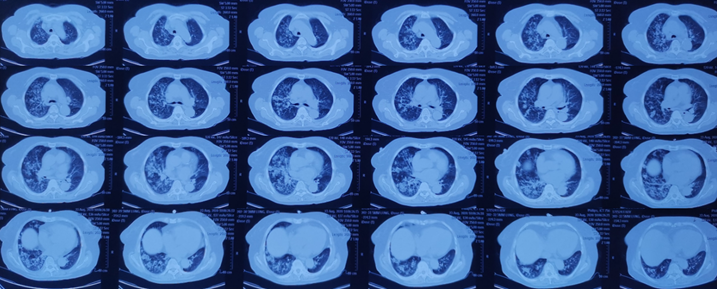

脂质性肺炎被认为由肺泡内含脂物质异物反应所致,脂质到达肺泡的机制:摄入(非挥发烃类)或吸入(挥发烃类),少数矿物油如汽油,即使经静脉注射也可导致肺损伤。在肺泡内,油脂乳化后被巨噬细胞吞噬,肺泡巨噬细胞不能代谢脂肪物质,当巨噬细胞死亡后油脂反复进入肺泡;油脂异常释放导致巨噬细胞肉芽肿反应、慢性炎症反应、肺泡及间隔纤维化;新鲜病灶显示肺泡被载脂巨噬细胞浸润,肺泡壁和间隔基本正常;进展性病灶显示巨大的空泡和肺泡壁、支气管壁和间隔炎性浸润,大量含脂空泡周围纤维化和实质破坏是晚期病变的特征。如果吸入矿物油或植物油,不易在体内分解,易在体内形成结节或肿块。如果吸入动物油,在体内可被分解为脂肪酸,导致炎症反应,局部肺水肿或肺出血。临床表现缺乏特异性,个体差异明显,从无症状到严重,甚至危及生命,常因患者年龄、吸入脂质的时间、数量及种类而不同。有症状的外源性脂质性肺炎常表现为慢性咳嗽或呼吸困难,其他表现为胸痛、咯血、间歇发热等。查体可发现叩诊浊音,听诊可闻及爆破音或干啰音。在长期持续进展性疾病患者中,体检可发现慢性缺氧,如杵状指。外源性类脂性肺炎可模拟许多其他肺部疾病,包括癌、肺炎、急性呼吸窘迫综合征和局部肉芽肿,HRCT最常见的表现是气腔实变、磨玻璃影、铺路石征、小叶间隔增厚、肿块样病变。急性外源性脂质性肺炎一般在吸入后半小时内出现肺部影像异常,大部分患者在24小时内出现肺部阴影,通常呈磨玻璃或实变影,一般在2周至8个月可逐渐改善或吸收,偶尔会遗留少许瘢痕纤维。慢性外源性脂质性肺炎最常见的影像学表现为一个或多个肺段的磨玻璃结节或实变影,通常在支气管周围分布,累及下叶最常见。实变可伴临近肺组织扭曲,在疾病晚期,由于油脂从肺泡内运送至肺间质,可出现增厚的小叶间隔或纤维化,还可见到铺路石征,也可表现为含脂质的结节或肿块影,由于慢性炎症及纤维化,肿块边界常不规则或有毛刺。下图为文献报道的一例急性外源性脂质性肺炎,患者胸部CT主要表现为实变,其中有液化坏死灶。下图为3例外源性脂质性肺炎患者的胸部CT,主要表现为肺结节/肿块和磨玻璃影。治疗3个月后,病变较轻者明显吸收。外源性脂质性肺炎的诊断主要基于暴露史,与疾病相符的影像学改变,唾液、支气管肺泡灌洗液或活检肺组织病理发现富含脂质的巨噬细胞,需要综合以上考虑诊断。支气管肺泡灌洗液的外观有提示价值,常为白色或浑浊液体,在表面可见脂肪漂浮层。